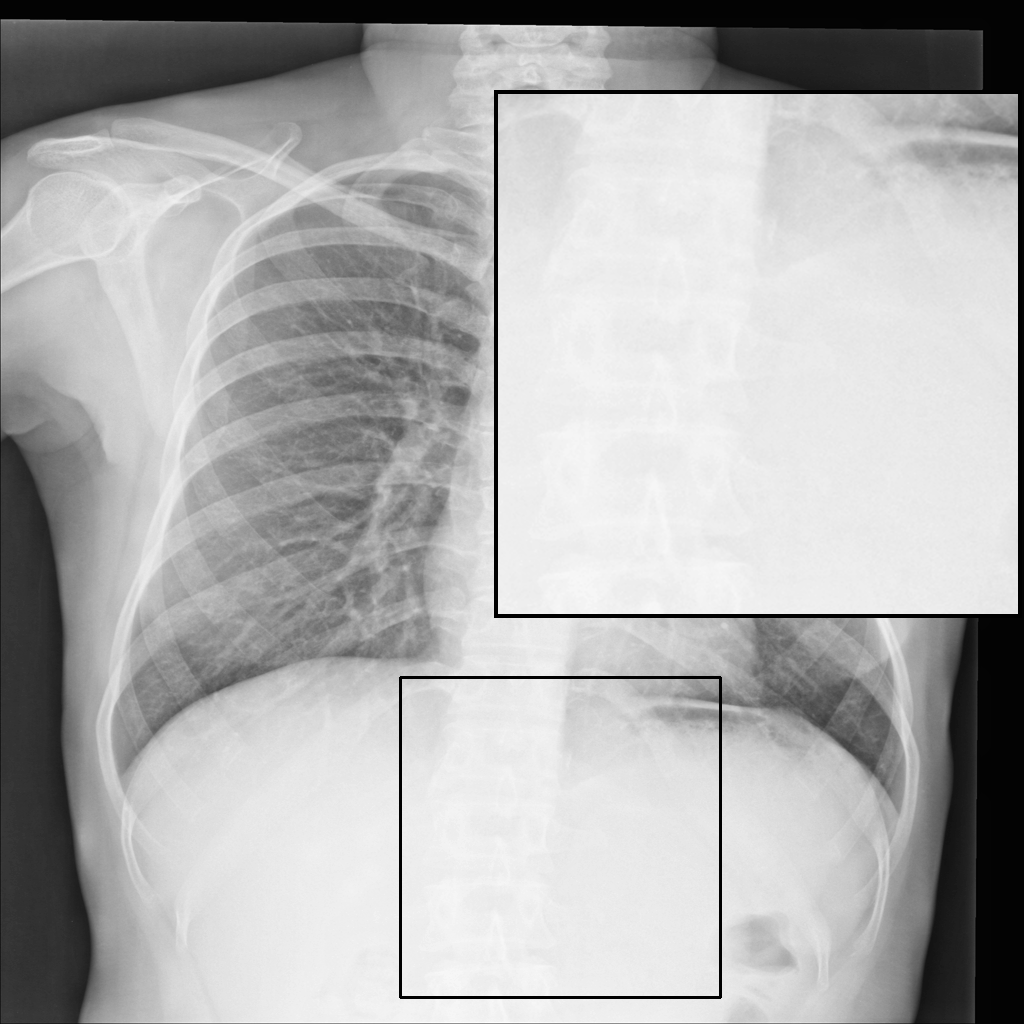

Fig. 3 shows image samples from the above datasets.

Figure 3: Image diversity across four datasets: (a) JSRT, (b) Montgomery County X-ray, (c) NIH ChestX-ray14, and (d) CheXpert